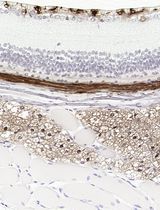

采用 Davidson 固定液和黑色素漂白法优化小鼠眼组织切片的免疫组化染色

Anne Nathalie Longakit [...] Catherine D. Van Raamsdonk

2025年11月20日 208 阅读